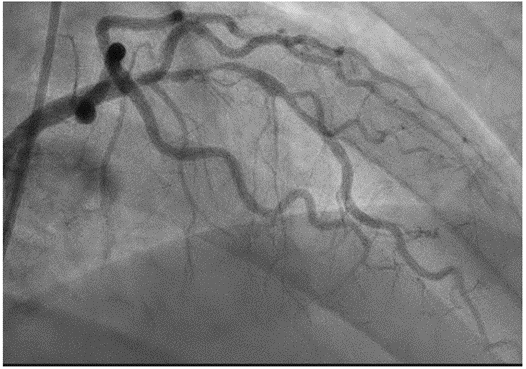

图1:初次冠脉造影

急诊行经皮冠状动脉介入治疗(PCI),于左回旋支(LCx)植入1枚药物洗脱支架。同期